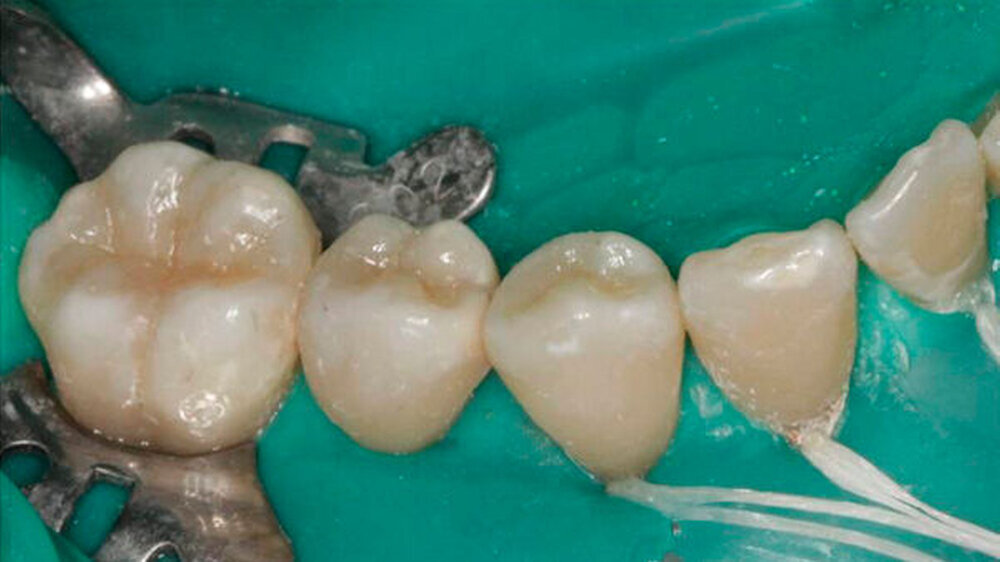

Die Restaurationen erfolgten minimal-invasiv. Durch Wiederherstellung der natürlichen Morphologie wurde für eine stabile Okklusion gesorgt. Auch bei der Kontrolle nach 9 Monaten machten die Füllungen morphologisch und farblich einen guten Eindruck. Ästhetik und Funktion gingen Hand in Hand.